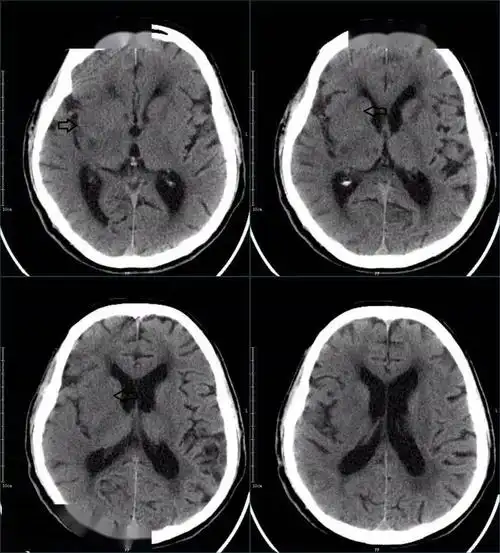

67超急性期大面积脑梗死ct平扫表现

外院ct平扫